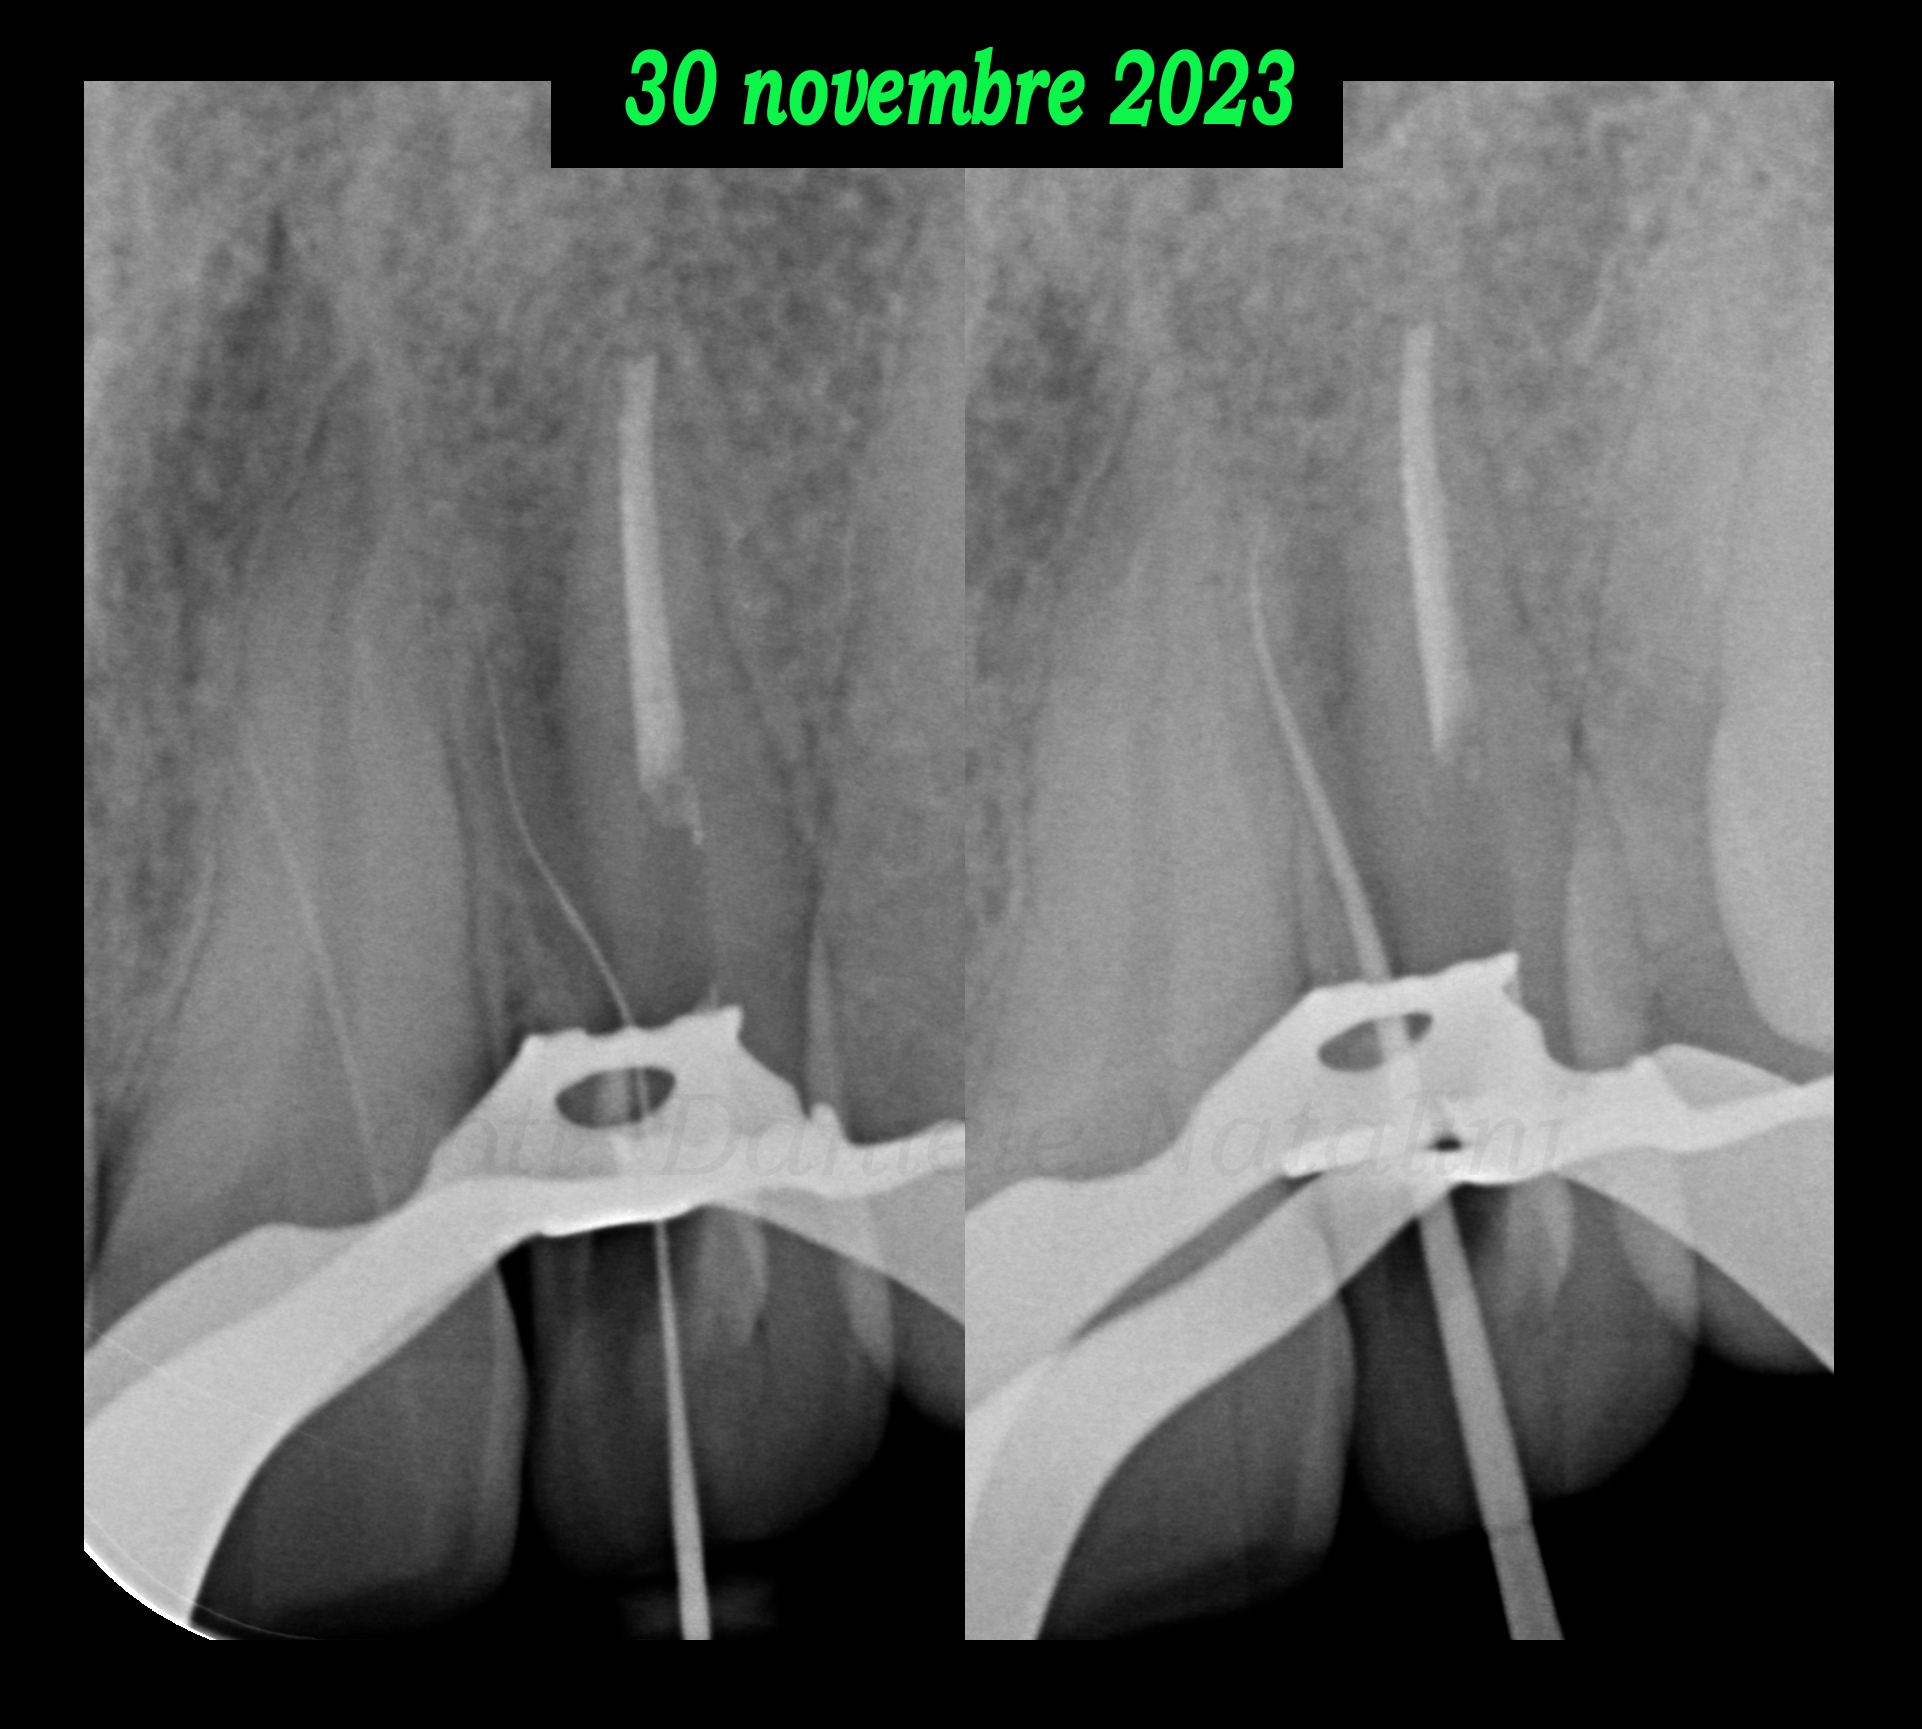

Il secondo appuntamento è a fine novembre 2023 e nel frattempo compare una fistola vestibolare.

Questa volta, tramite gli ultrasuoni, il Dr. Natalini si dirige nell’angolo mesio-palatale e, nonostante non ci sia un orifizio chiaramente visibile, ad un certo punto un file manuale 08 si impegna ed avanza a fatica con il rilevatore elettronico che, a sua volta, progressivamente arriva a segnalare l’apice.

Vista la forma anomala e la dimensione ridotta della radice accessoria, dopo i passaggi con Komet Skytaper 15/03 e 20/03, il Dr. Natalini riesce ad arrivare senza forzare, come ultimo passaggio, con un FQ 25/04 a 2 mm dall’apice, la cui rifinitura, viene completata manualmente sempre con un file 25.

La chiusura è effettuata con cono singolo e bioceramico Komet BioSeal.

Il secondo appuntamento è a fine novembre 2023 e nel frattempo compare una fistola vestibolare.

Evidenza di una fistola vestibolareQuesta volta, tramite gli ultrasuoni, il Dr. Natalini si dirige nell’angolo mesio-palatale e, nonostante non ci sia un orifizio chiaramente visibile, ad un certo punto un file manuale 08 si impegna ed avanza a fatica con il rilevatore elettronico che, a sua volta, progressivamente arriva a segnalare l’apice.

Trattamento endodontico di un incisivo laterale superiore con due radici - parte 10Vista la forma anomala e la dimensione ridotta della radice accessoria, dopo i passaggi con Komet Skytaper 15/03 e 20/03, il Dr. Natalini riesce ad arrivare senza forzare, come ultimo passaggio, con un FQ 25/04 a 2 mm dall’apice, la cui rifinitura, viene completata manualmente sempre con un file 25.

Trattamento endodontico di un incisivo laterale superiore con due radici - parte 12La chiusura è effettuata con cono singolo e bioceramico Komet BioSeal.